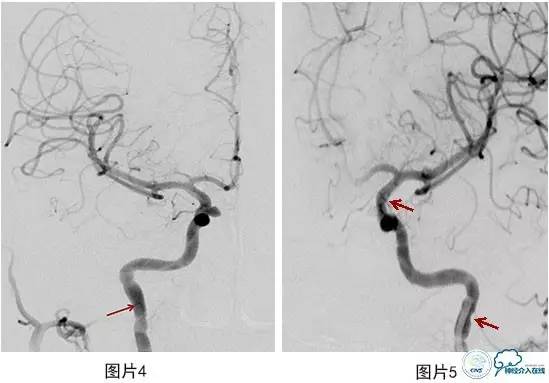

病例2:患者女,39岁。右侧颈眼动脉瘤,上导引导管时出现血管痉挛,经导引导管内使用尼莫地平后缓解(图4)。使用4.5 mm×20 mm LVIS支架辅助栓塞,术中出现近端血管痉挛,支架内血栓形成(图5),远端血流缓慢,额顶升支血栓形成(图6)。即刻追加肝素化,尼莫地平,维持收缩压,替罗非班15ml经导引导管内注入后近端血管痉挛解除(图7),额顶升支血管大部分再通(图8),可见后循环软膜支吻合(图9)。

图4上导引导管时出现血管痉挛

图5 近端血管痉挛,支架内血栓形成